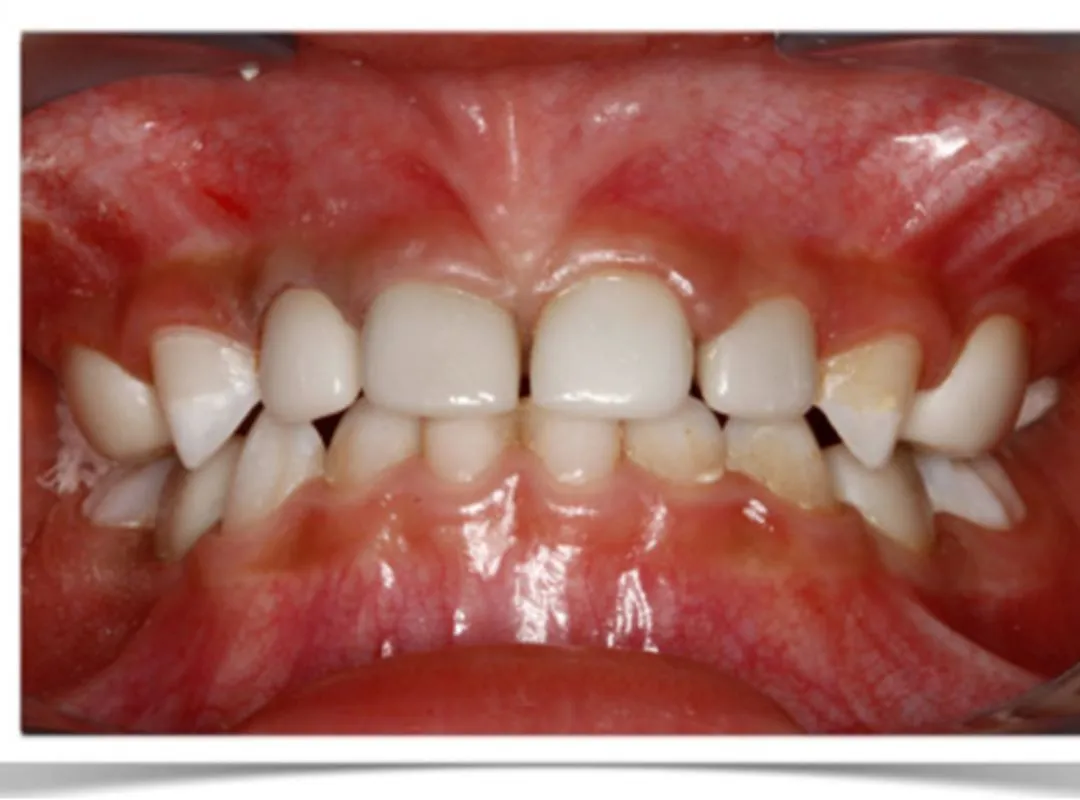

Orthodontics Modern braces and alignment treatments designed to create healthy, beautiful smiles.

I had undergone my teeth Aligner process at JP dental, Perambur,which was over a period of 8 months. Journey was of 12 levels of aligners and after each level my teeth were thoroughly evaluated to ensure the process was smooth and progressive. The doctors here are very professional and have upto date equipments which gave me a very great outcome from my journey here. Highly recommend .create a caption for this review